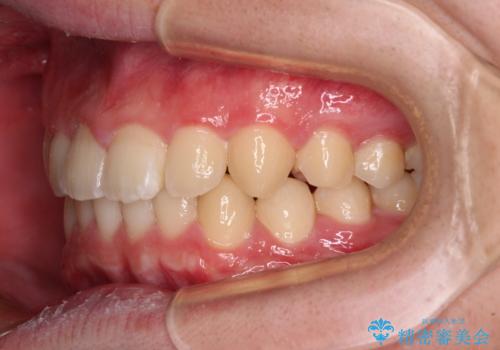

- 前方に傾斜した前歯を気にして来院された患者様です。

強く食いしばってしまう癖があり、下顎前歯に押し出されて上顎前歯が前方へ斜めに突き出している状態でした。

IPR(歯と歯の間を削る)を多用して、インビザラインにて矯正治療を行うこととしました。

口元を引っ込めるためのゴムかけを頑張っていただき、満足のいく上顎前歯の傾斜へ改善することができました。